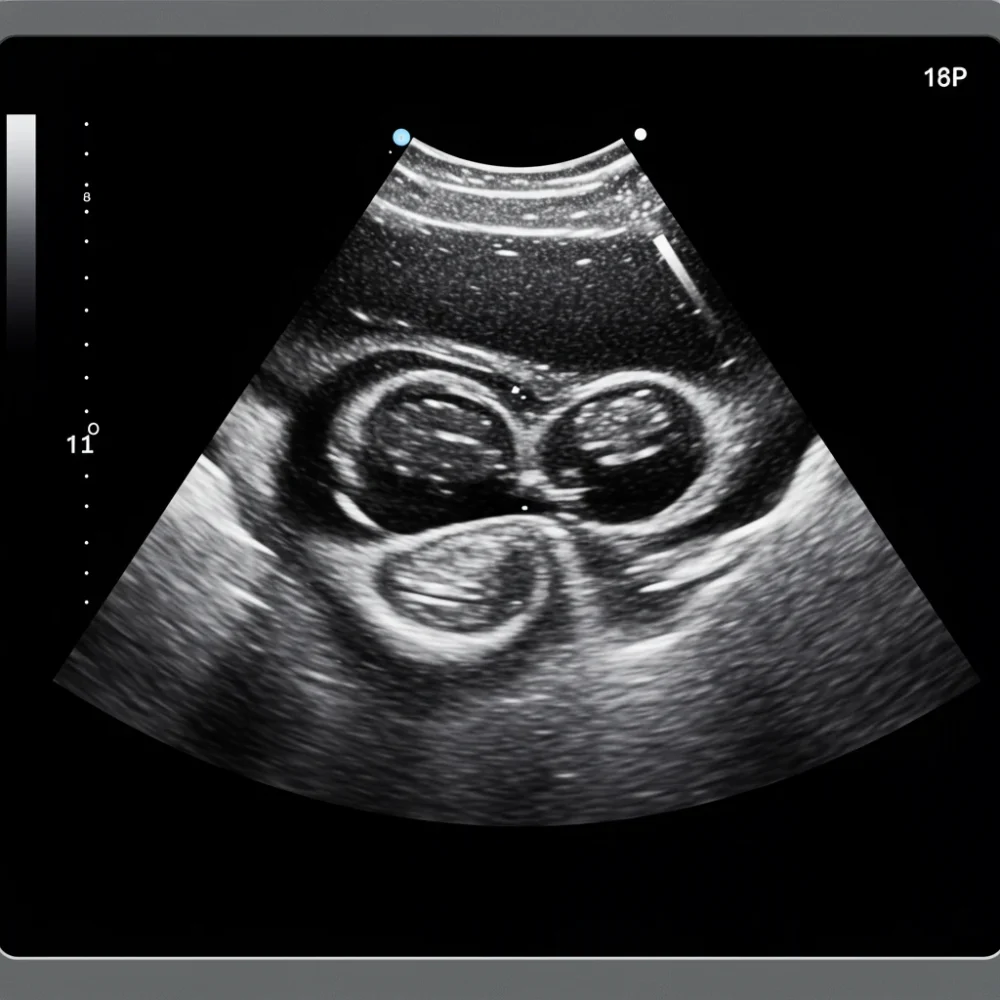

이 검사는 인체에 해가 없는 고주파 음파(초음파)를 신체 조직 내부로 보냈다가, 각 조직에서 반사되어 돌아오는 음파를 실시간 영상으로 변환하는 방식으로 진행된다. 방사선을 전혀 사용하지 않기 때문에 임신 중이거나 어린 영유아에게도 안전하게 적용할 수 있다는 점이 큰 장점으로 부각된다. 또한, 검사 과정에서 통증이 거의 없어 환자의 불안감을 최소화하며 편안하게 검사를 받을 수 있다.

초음파는 특히 물이나 연부 조직을 잘 통과하는 성질이 있어 복부 장기, 갑상선, 유방 등 부드러운 조직이나 액체가 많은 부위의 진단에 매우 유용하게 활용된다. 주요 장기의 크기, 형태 변화는 물론 혹이나 결석 유무, 심지어 혈관 내 혈류 흐름까지 실시간으로 관찰할 수 있어 질병의 조기 발견과 정확한 진단에 핵심적인 역할을 수행한다.

복부, 갑상선, 유방 외에도 초음파 검사는 우리 몸의 여러 부위에 적용된다. 여성의 자궁과 난소 등 골반 장기, 남성의 전립선과 고환 등 비뇨생식기 질환 진단에 사용되며, 근육이나 힘줄 손상, 관절 주변의 염증 등 연부 조직의 이상을 살피는 데도 활용도가 높다. 심장의 구조와 기능을 평가하는 심장 초음파(심초음파) 역시 초음파 검사의 중요한 분야 중 하나다.